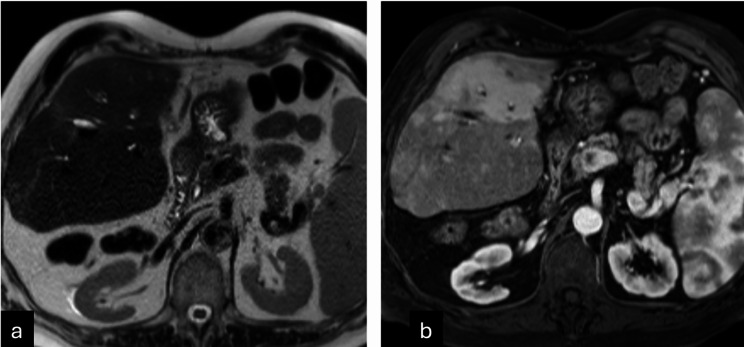

背景:通过肝移植前横断面成像准确评估肝细胞癌存活情况对于肝移植后正确的器官分配和患者的整体预后非常重要。目的:通过对比增强多期CT和MRI,确定LI-RADS TRA与外植体病理在热消融患者中的准确性。材料和方法:由三名委员会认证的放射科医生对2001年3月至2019年9月在一家三级医院接受热消融和肝移植治疗的119例连续成人HCC患者的影像学研究进行回顾性研究。将每个肿瘤的LI-RADS TRA分类与外植体病理进行比较。采用Cohens Kappa检验和Fleiss κ检验,95%置信区间采用bootstrap技术。结果:经皮热消融治疗的119例hcc患者(中位年龄59岁,男性95例[80%])中,68%完全坏死,32%病理存活。在外植体上存活的肿瘤在治疗前成像时较大(中位数为2.4 vs. 2.1 cm;P = 0.02),组间移植前消融腔大小无差异(分别为4.0和3.9 cm;p = 0.58)。LI-RADS TRA对存活肿瘤的NPV为71% (68-74);PPV为62.5% (39 ~ 81)(p = 0.01),敏感性为19%(9.4 ~ 32),特异性为95%(89 ~ 98),准确性为70%(63 ~ 77)。在外植体上,33例患者中发现55例意外治疗naïve移植前成像不可见的存活肿瘤。结论:即使应用于相对均匀的经皮消融队列,LI-RADS TRA的“不可存活”类别在预测肿瘤缺失方面也表现出较低的敏感性。与外植体病理相比,MRI在预测肿瘤生存能力方面比CT更准确。

Results: Of the 119 patients (median age 59 years, 95 [80%] male) with 165 HCCs treated with percutaneous thermal ablation, 68% were completely necrotic and 32% were viable on pathologic analysis. Tumors viable on explant were larger on pre-treatment imaging (median 2.4 vs. 2.1 cm; p = 0.02) with no difference in pre-transplant ablation cavity sizes between groups (4.0 vs. 3.9 cm, respectively; p = 0.58). NPV of LI-RADS TRA for viable tumor was 71% (68-74); PPV of 62.5% (39-81) (p = 0.01) with a sensitivity of 19% (9.4-32), specificity of 95% (89-98), and accuracy of 70% (63-77). On explant, 55 incidental treatment naïve viable tumors, not visible on pre-transplant imaging, were found in 33 patients.

Conclusion: The "non-viable" category of LI-RADS TRA even when applied to a relatively uniform percutaneous ablation cohort, demonstrated low sensitivity in predicting absence of viable tumor. MRI had more accuracy than CT in predicting tumor viability when compared to explant pathology.